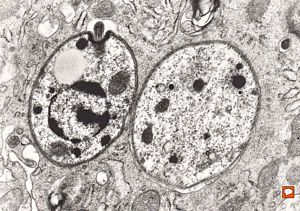

M, 11y. | mycosis fungoides v.s. - cerebriform nucleus of Sézary cell

F, 57y. | mycosis fungoides … cerebriform nucleus of Sézary cell

F, 37y. | mycosis fungoides … cerebriform nucleus of Sézary cell